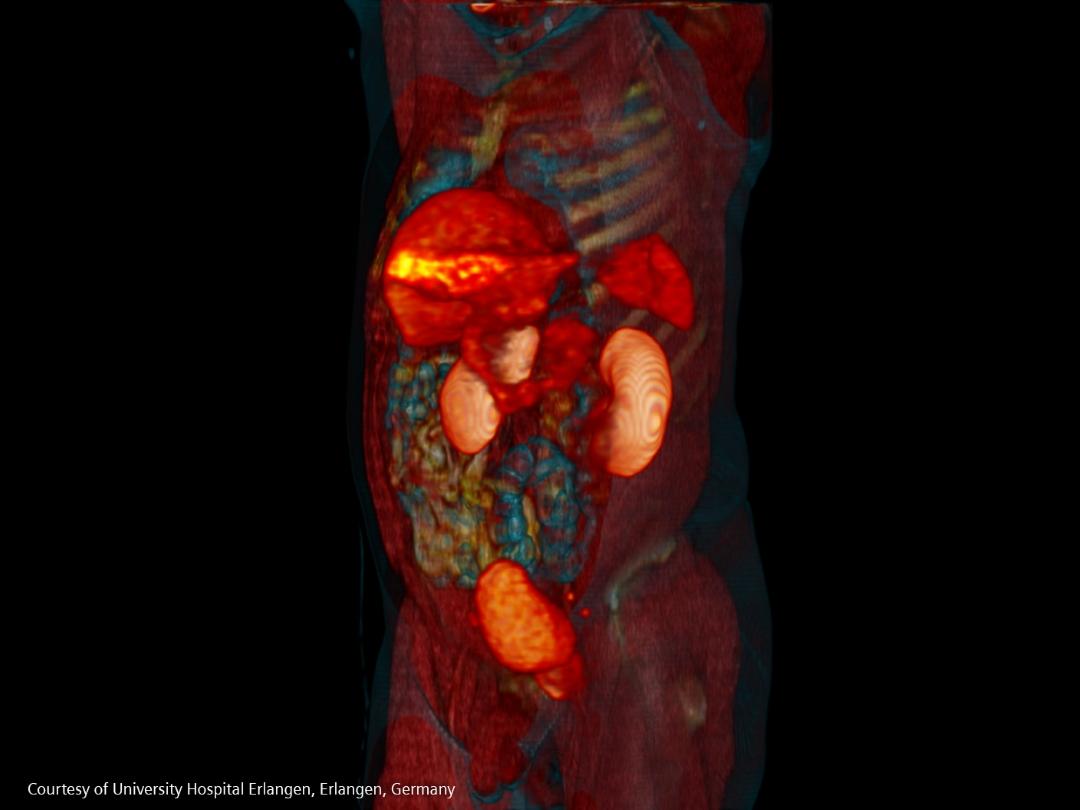

Most often men are diagnosed with localized disease, but 10–20 percent are diagnosed with metastatic disease and of those battling localized disease, 20–30 percent will develop metastases [25].

70 percent of those diagnosed with advanced prostate cancer and 90 percent of men who succumb to the disease have bone metastases [25].